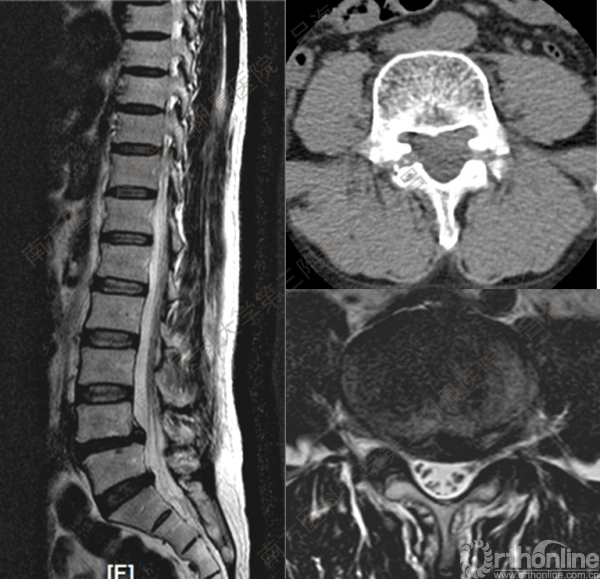

随着社会老龄化进程加快,胸腰椎退行性病变的治疗已经成为脊柱学术界的一个热点话题。MIS-TLIF手术可以治疗多种不同的胸腰椎退行性疾病,南方医科大学第三附属医院吕海教授结合病例为我们一一展示了该术式在治疗不同胸腰椎疾病时的具体手术过程。